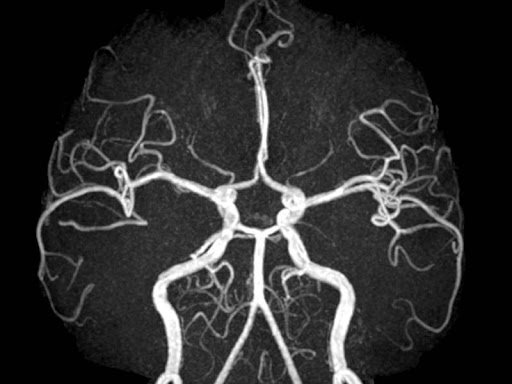

Chụp cộng hưởng từ động mạch chủ ngực có phạm vi sử dụng khá rộng rãi, đáp ứng vai trò chẩn đoán và điều trị cho nhiều bệnh lý khác nhau của động mạch chủ ngực.

Chỉ định chụp cộng hưởng từ động mạch chủ ngực bao gồm:

- Phát hiện các bất thường như phình mạch, bóc tách động mạch ở động mạch chủ ngực, hoặc ở các phân nhánh của động mạch chủ ngực.

- Phát hiện bệnh lý Xơ vữa động mạch ở các vị trí quan trọng như động mạch cảnh, nguyên nhân gây đột quỵ.

- Đánh giá được mức độ hẹp và các mạch máu có liên quan trong bệnh lý mạch máu, hỗ trợ cho kế hoạch điều trị can thiệp mạch vành.

- Chẩn đoán các bất thường mạch máu bẩm sinh ở trẻ em.

- Thay thế chụp cắt lớp vi tính động mạch chủ ngực khi thuốc cản quang có nguồn gốc từ iot bị chống chỉ định.